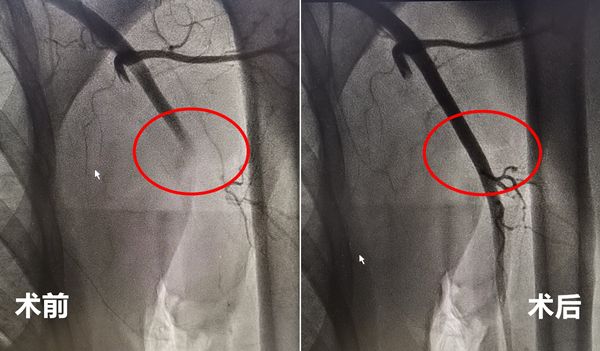

华体会体育 心内科团队迅速展开急诊手术,既要清除血栓,又要防止血栓脱落继续向远端栓塞,还要精准将患者手臂的血流重新建立起来。不到一小时,大量暗红色血凝块经由导管被抽吸出体外,堵塞的血管及时恢复了畅通。患者紫色而冰凉的手臂逐渐变红温暖,血管充盈起来,疼痛症状也立即缓解,黄大叔紧锁的眉头终于舒展开来。